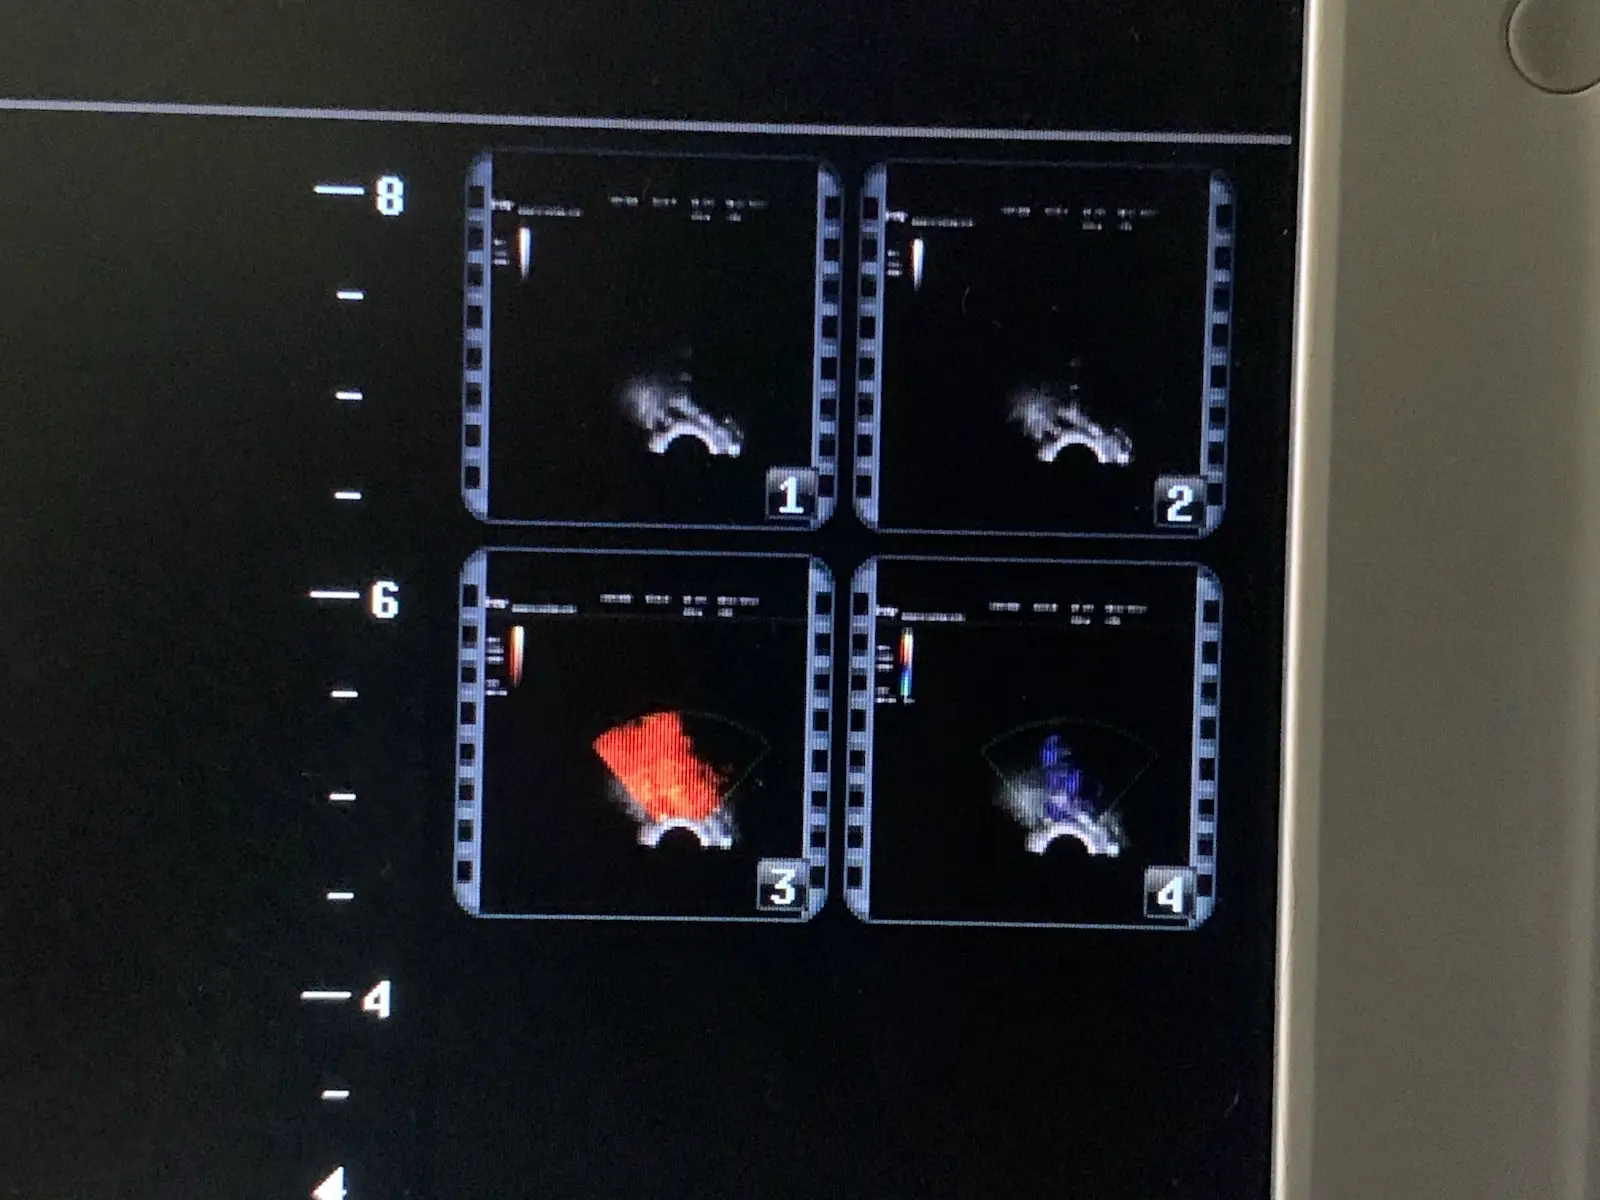

Condition: Used, working

Brand: Mindray

Model: V10-4s

Probe Type: Endocavity / Transvaginal / Micro-convex

Applications: OB/GYN, Urology, Veterinary

Up for sale is a genuine Mindray V10-4s curved array endocavity probe. This transducer is designed for high-resolution imaging in obstetrics, gynecology, and urology. It features a wide-band frequency range (4–10 MHz) and a small 10mm radius for patient comfort.

Source: Removed from a clinical environment. The probe was tested on a Mindray MR-M7 Ultrasound unit to confirm full functionality, image quality, and connectivity.